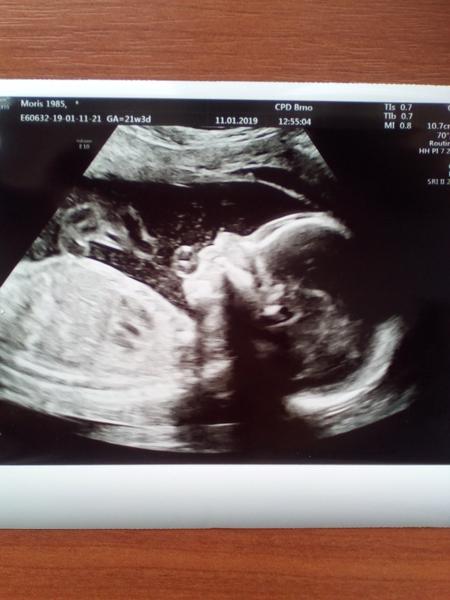

@lazuli35 taky jsem se bála,kor po tom všem,nastěstí to vypadá že i hemtom je fuc a taky jsme si počkala,šla jsem až 22tt,mezi posledníma